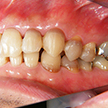

6. 初診時左側

右側の八重歯が相当飛び出しているのが目立ちます。これでは口唇を咬みそうです。閉口障害となり同部が乾燥して良好な環境ではありません。治療方針として八重歯を何とかしたいと考えます。